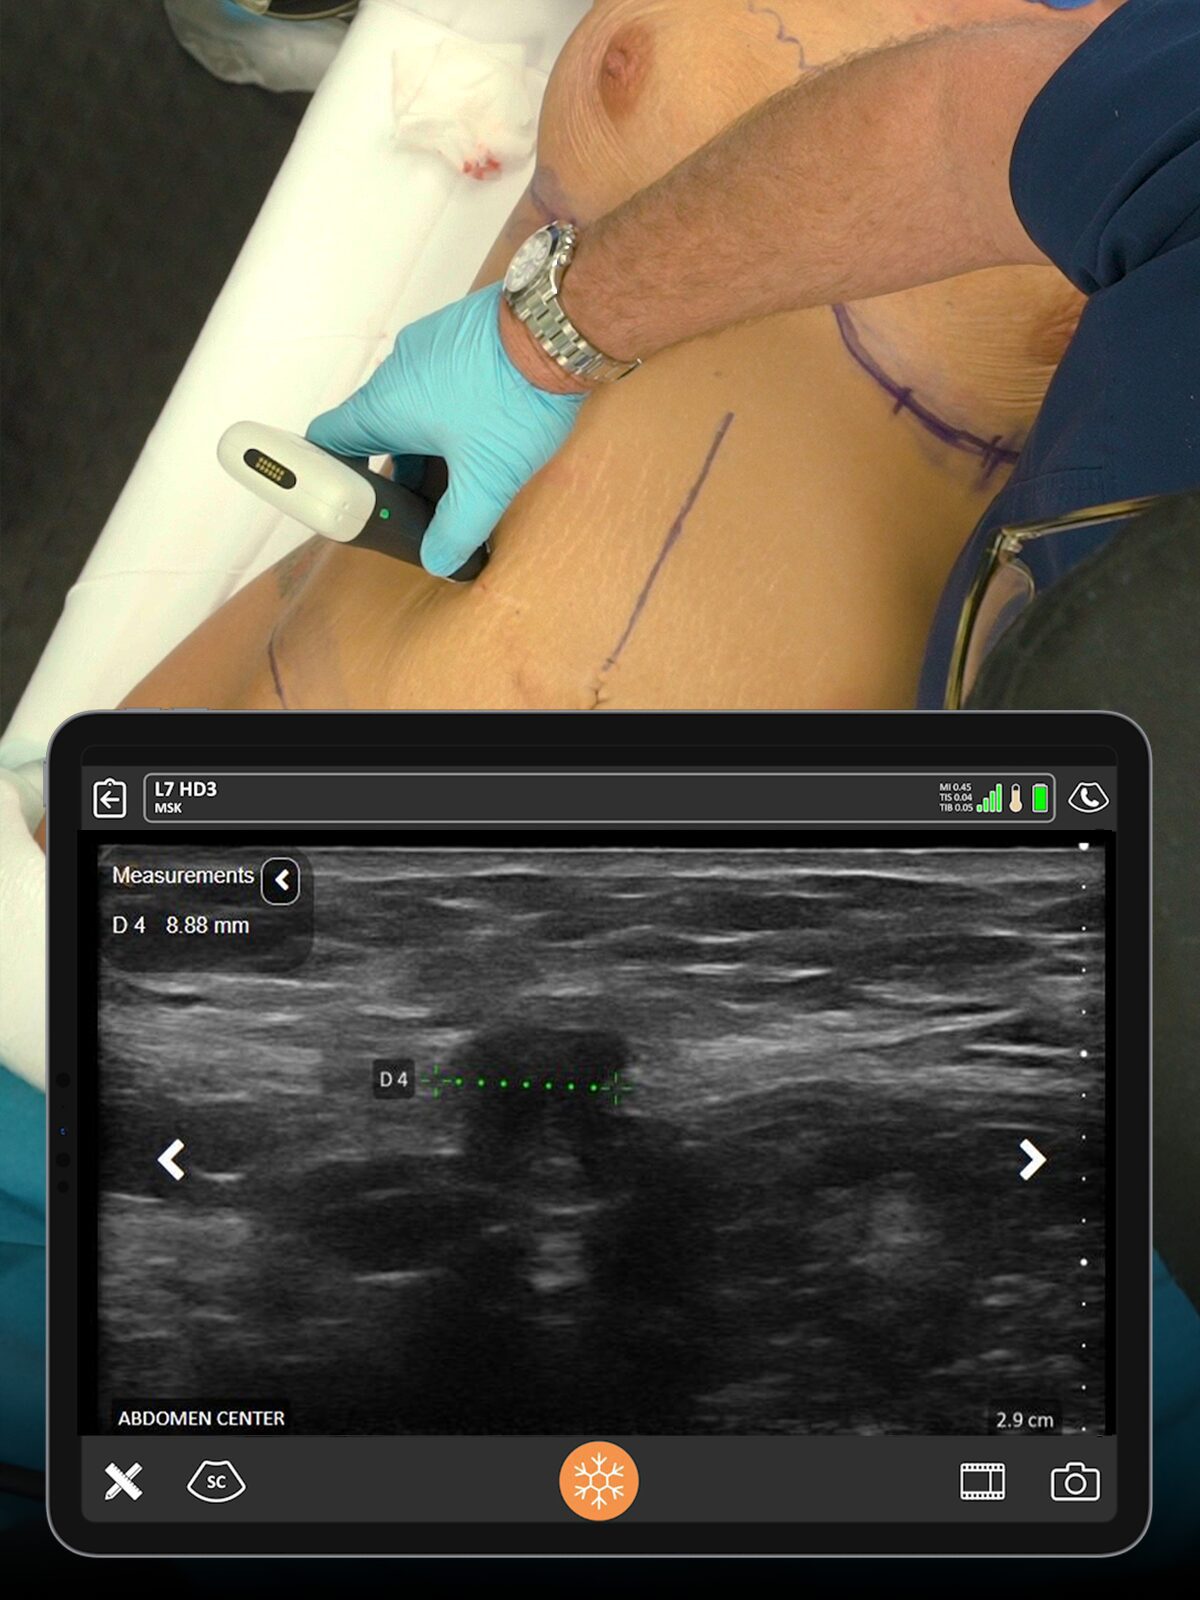

From patient assessments, abdominal defect screening, confirmation of fat stores, and monitoring for hematomas or seromas, ultrasound can enhance your patient care.